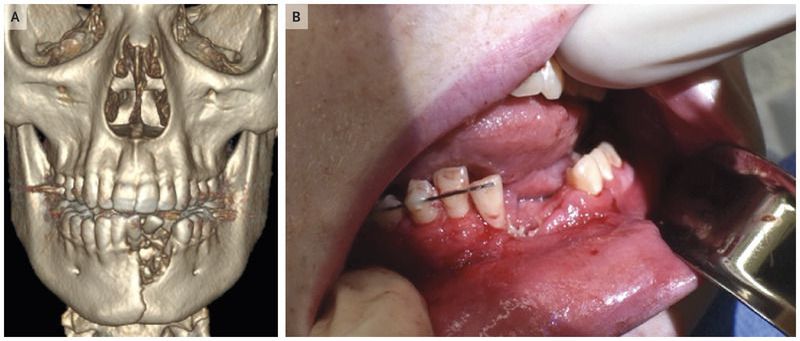

A 17-year-old boy presented to the emergency department with pain and swelling in his jaw 2 hours after an e-cigarette exploded during use. The patient was in a hemodynamically stable condition and had no respiratory distress. He had a circular puncture to the chin, extensive lacerations in his mouth, multiple disrupted lower incisors, and bony incongruity of the left mandible. Reconstructed computed tomography of the head revealed a comminuted and displaced mandibular fracture with disruption of the left central and lateral incisors (Panel A). The patient underwent open reduction and internal fixation of the fracture, dental extraction, and débridement of devitalized tissue. The increasing prevalence of vaping among adolescents is a public health concern. At the 6-week follow-up assessment, the patient had recovered well, and the mandibular–maxillary fixation was removed (Panel B).